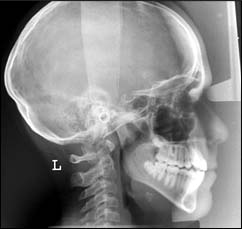

TÉLÉRADIOGRAPHIE DE PROFIL ET DE FACE :